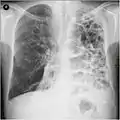

انجام رادیوگرافی قفسه سینه و شمارش کامل خون ممکن است در زمان تشخیص، احتمال ابتلا به شرایط دیگر را از میان بردارد.[49] نشانههای مخصوص در رادیوگرافی شامل گشاد شدن ششها، دیافراگم صاف، فضای خالی افزایش یافته پشت جناغ و آبکیسه میباشد، این در حالی است که میتواند بیماریهای ریوی دیگر مانند سینهپهلو، اِدِم ریه یا پنوموتوراکس را شامل نشود.[50] اسکن رزلوشن بالای توموگرافی رایانهای از سینه ممکن است پخش آمفیزم در ریه را نشان دهد و میتواند احتمال ابتلا به بیماریهای ریوی دیگر را از میان بردارد.[2] این مورد، غیر از مواقعی که عمل جراحی انجام شدهاست، به ندرت بر مدیریت بیماری تأثیر میگذارد. فشار گاز خون شریانی برای تعیین نیاز به اکسیژن استفاده میشود و برای افرادی که FEV1 آنها کمتر از ۳۵٪ پیشبینی شدهاست، افرادی که اشباع اکسیژن خون آنها کمتر از ۹۲٪ است و افرادی که علائم نارسایی احتقانی قلبی دارند توصیه میشود. در مناطقی از جهان که نقص آنتی تریپسین آلفا-۱ شایع است، باید از افراد دچار COPD (مخصوصاً افراد زیر ۴۵ سال که آمفیزم روی قسمتهای تحتانی ریههایشان اثر گذاشتهاست) آزمایش گرفته شود.[8]

Lung bulla as seen on CXR in a person with severe COPD

A severe case of bullous emphysema

Axial CT image of the lung of a person with end-stage bullous emphysema.